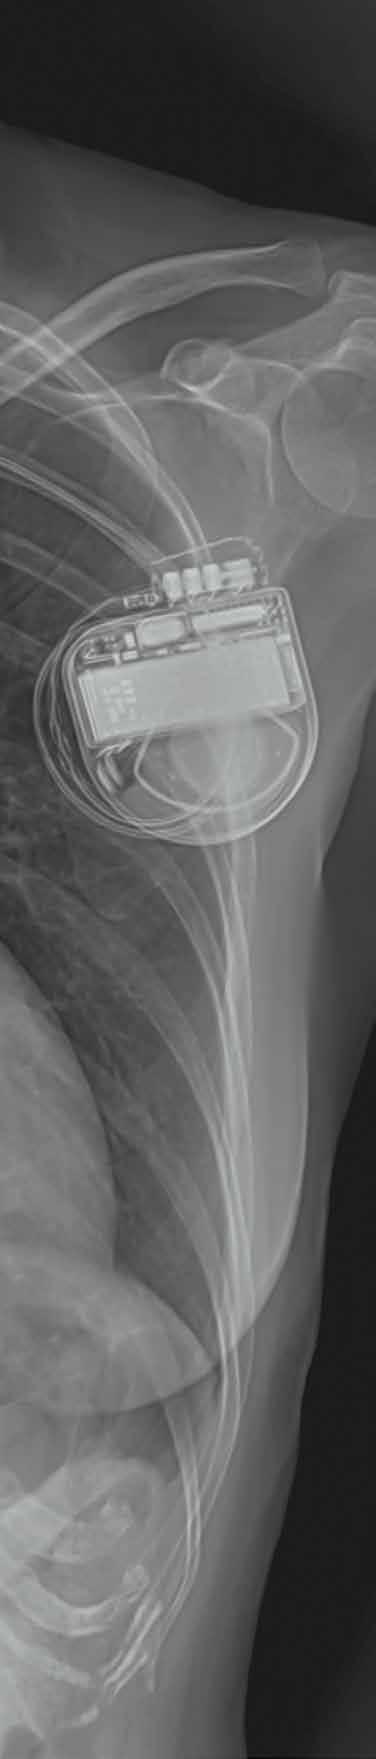

Welche Arten von Herzschrittmachern gibt es?

Heute können wir das Herz auf verschiedene Arten stimulieren: Der Einkammerschrittmacher hält das Herz mit einer Elektrode in Gang. Der Zweikammerschrittmacher stimmt zusätzlich die Frequenz der Vorhöfe und der Herzkammern aufeinander ab. Den Dreikammerschrittmacher setzen wir insbesondere bei Patienten mit einer Herzschwäche ein, damit der Herzmuskel wieder an Kraft gewinnt und synchroner schlägt. Seit einigen Jahren gibt es ausserdem sogenannte elektrodenlose, intrakardiale Schrittmacher. Sie werden direkt ins Herz eingesetzt, sind rund 14-mal kleiner als herkömmliche Geräte und wiegen weniger als zwei Gramm.

Herzschrittmacher

6000 werden im Schnitt in der Schweiz jährlich implantiert; 200 kardiologische Eingriffe verzeichnet das KSB im Jahr.

1,75 Gramm wiegen die kleinsten Herzschrittmacher. Das entspricht etwa dem Gewicht eines Gummibärchens.

Lebensretter aus der Blechdose

Die Geschichte des Herzschrittmachers beginnt vor 65 Jahren, und das kam so: Nach einer Austernvergiftung litt der 43-jährige Arne Larsson an Herzrhythmusstörungen. Sein Herz schlug nur noch 28 Mal pro Minute und setzte täglich bis zu 30 Mal aus. Dabei rettete ihm seine Ehefrau Else-Marie mehrfach das Leben, indem sie ihm jeweils heftig auf den Brustkorb schlug. Das war natürlich kein Zustand für eine gesunde Ehe. Eines Tages entdeckte sie in der Zeitung einen Artikel, der alles verändern sollte. Else-Marie erfuhr, dass Ingenieur Rune Elmqvist und Kardiologe Åke Senning in der Nähe von Stockholm an einem Herzschrittmacher bastelten. Sie kontaktierte die beiden und überzeugte sie, ihrem Arne zu helfen. Die beiden waren skeptisch, denn sie hatten ihre Idee erst an Tieren getestet.

Doch Else-Marie liess nicht locker, und so entschieden sich Arzt und Techniker, Arne heimlich notfallmässig zu operieren. Rune baute zwei Transistoren und eine kleine Batterie in eine leere Schuhwichsedose ein, die er mit Kunstharz ausgoss: Rund 240 Gramm wog dieser Prototyp, fast zehnmal

so viel wie heutige Standardmodelle. Doch an der Zuverlässigkeit und Leistungsfähigkeit mussten die beiden noch schrauben: Der erste Schrittmacher der Medizingeschichte versagte bereits nach fünf Stunden – sein Nachfolger schaffte bereits eine Woche. In den folgenden 43 Jahren erlebte Arne Larsson die Erfolgsgeschichte des Herzschrittmachers Schritt für Schritt am eigenen Leib mit: Insgesamt 26 Ausführungen pflanzten ihm die Ärzte ein. Heute garantieren moderne Herzschrittmacher Herzkranken eine fast normale Lebenserwartung. Dies galt auch für Arne Larsson: Er starb im Alter von 86 Jahren – nicht etwa an Herzversagen, sondern an Hautkrebs.

Seit Jahren werden Herzschrittmacher routinemässig «eingebaut». 6000 solcher Impulsgeber werden jährlich in der Schweiz implantiert, weltweit sind es mehr als eine Million. Übrigens spielt auch die Schweiz eine Rolle in unserer Geschichte. Åke Senning übernahm 1961 den Lehrstuhl für Chirurgie an der Universität Zürich, wo er 1969 die erste Herztransplantation in der Schweiz durchführte.

Der erste Herzschrittmacher der Geschichte aus dem Jahr 1958.